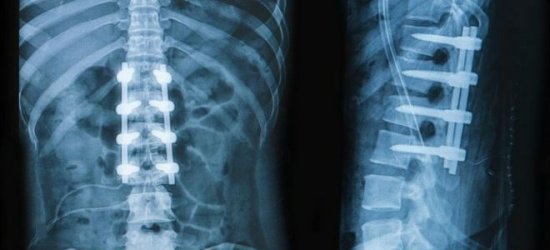

Патологии позвоночника

Механизм развития заболеваний в этой области может быть различным. Чаще всего диагностируют раздражение нервных корешков, отходящих от спинного мозга. Это вызывает сильные боли, которые могут локализоваться не только в области нервных окончаний, но и распространяться дальше. Также наблюдаются напряжение связок и спазмы мышц, что усугубляет состояние.

Боль в нижней части спины может определить только врач. Не следует заниматься самодиагностикой и самолечением. Диагноз ставится на основе жалоб пациента, клинических проявлений, анамнеза и результатов инструментальных исследований. Обычно назначают рентгенографию, миелографию, МРТ, КТ и другие обследования.

Компьютерная томография — это эффективный метод для выявления структурных изменений в позвоночнике, вызванных травмами, инфекциями, опухолями, остеопорозом и другими заболеваниями. Миелография использует контрастное вещество и применяется при подозрении на стеноз позвоночного канала, грыжи, опухоли и другие патологии.